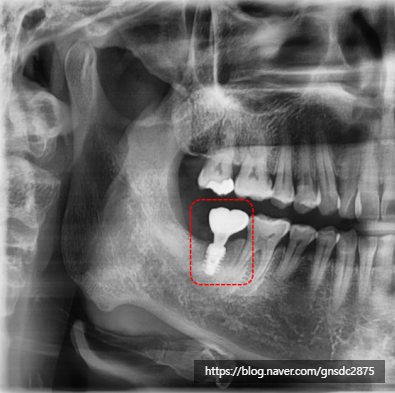

사랑니 통증 방치 사례

다음은 실제 사랑니 통증을 방치하다

뒤늦게 발치를 진행한 사례입니다.

#CASE

사랑니 통증 방치 후

잇몸뼈 소실

해당 환자분은 사랑니쪽의

지속적인 통증을 느껴오셨으나

일이 바빠 약을 먹으며 버티시다

극심한 통증으로

뒤늦게 발치를 진행한 케이스입니다.

상태를 확인해보자

방치된 사랑니 주변 염증으로

옆 어금니의 잇몸뼈가 소실되어

뿌리가 지탱하지 못해 흔들리는 상태였습니다.

빨간색:사랑니 / 파란색:어금니 / 빨간선:소실된 잇몸

겉으로 보기엔 초기충치 정도만 진행되어

신경치료를 진행해 최대한 살리고 싶었지만

사랑니와 함께 옆어금니도 함께 발치하여

어금니는 뼈이식 후 임플란트를 하기로 결정했습니다.